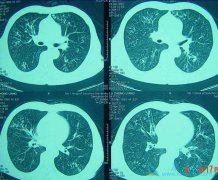

转移性肺癌的意思就是在患者体内的任何位置的恶性肿瘤都是通过各种方式转移到患者的肺部。大约有60%的恶性肿瘤在初次检查时就有肿瘤转移,其中30%~50%肿瘤转移到肺部。像不同的肿瘤转移到肺部的发生率不同,其中,甲状腺癌、乳腺癌、肾癌、绒毛膜癌、骨 ...